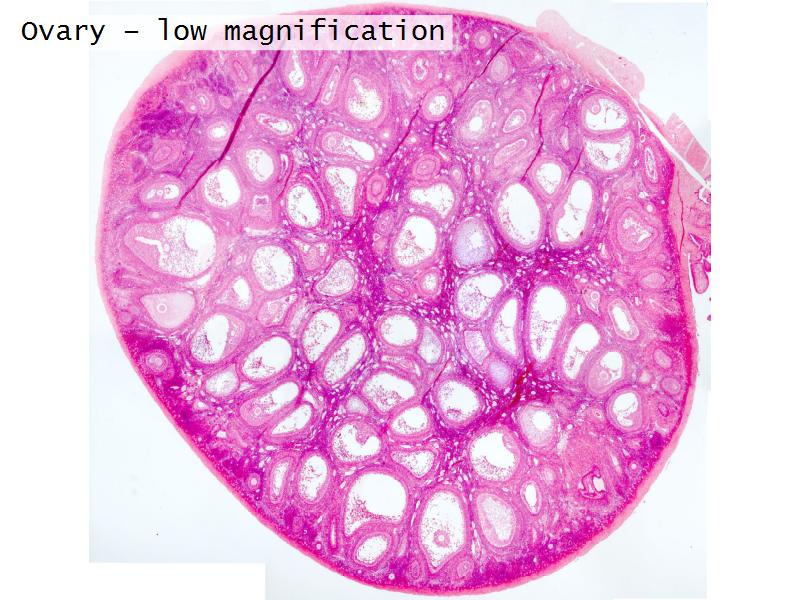

- Ovary

- Slide 89/106: Ovary